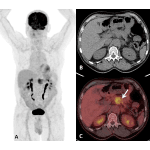

Theragnostic nuclear medicine is a much discussed topic in nuclear medicine and is currently discussed and debated in clinical oncology with great interest and optimism. Radionuclide theragnostics generally pairs diagnostic biomarkers with radiolabelled therapeutic agents that share a specific target within the diseased cells or tissues. The clinical indications are expanding, with evolving evidence. Incorporating […]